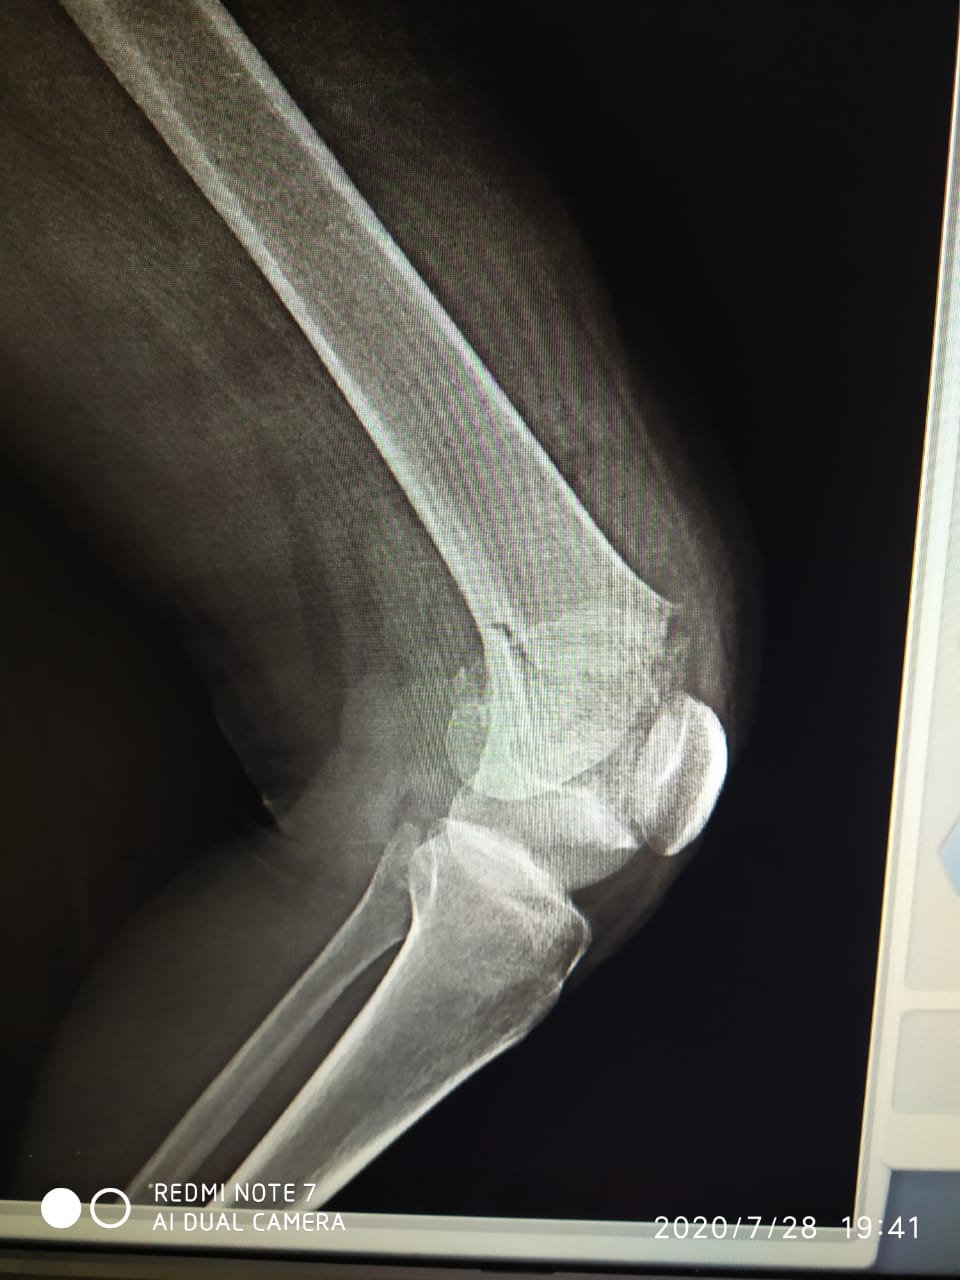

Por conta da colisão, a jovem sofreu uma fratura no joelho, quebrando o o fêmur. De acordo com a família, a cirurgia custa em torno de R$ 13.500 reais.